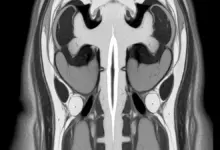

Alterações degenerativas da coluna cervical

Com o passar dos anos, é comum surgir desgaste nas articulações e discos do pescoço, quadro conhecido como espondilose cervical.

Em algumas pessoas, esse processo causa inflamação, compressão de nervos e dor que começa na cervical e alcança a cabeça.

Hérnia de disco cervical

Quando parte do disco entre as vértebras se desloca, pode comprimir raízes nervosas e estruturas ao redor.

O resultado é dor na região do pescoço, que muitas vezes acompanha irradiação para a cabeça, ombros e braços, formigamento ou perda de força.